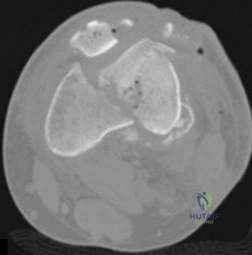

Question 24

A 45-year-old female sustains a high-energy supracondylar femur fracture. Computed tomography reveals a displaced coronal shear fracture of the lateral femoral condyle (Hoffa fragment).

What is the most biomechanically sound fixation strategy for this specific fragment?

Explanation